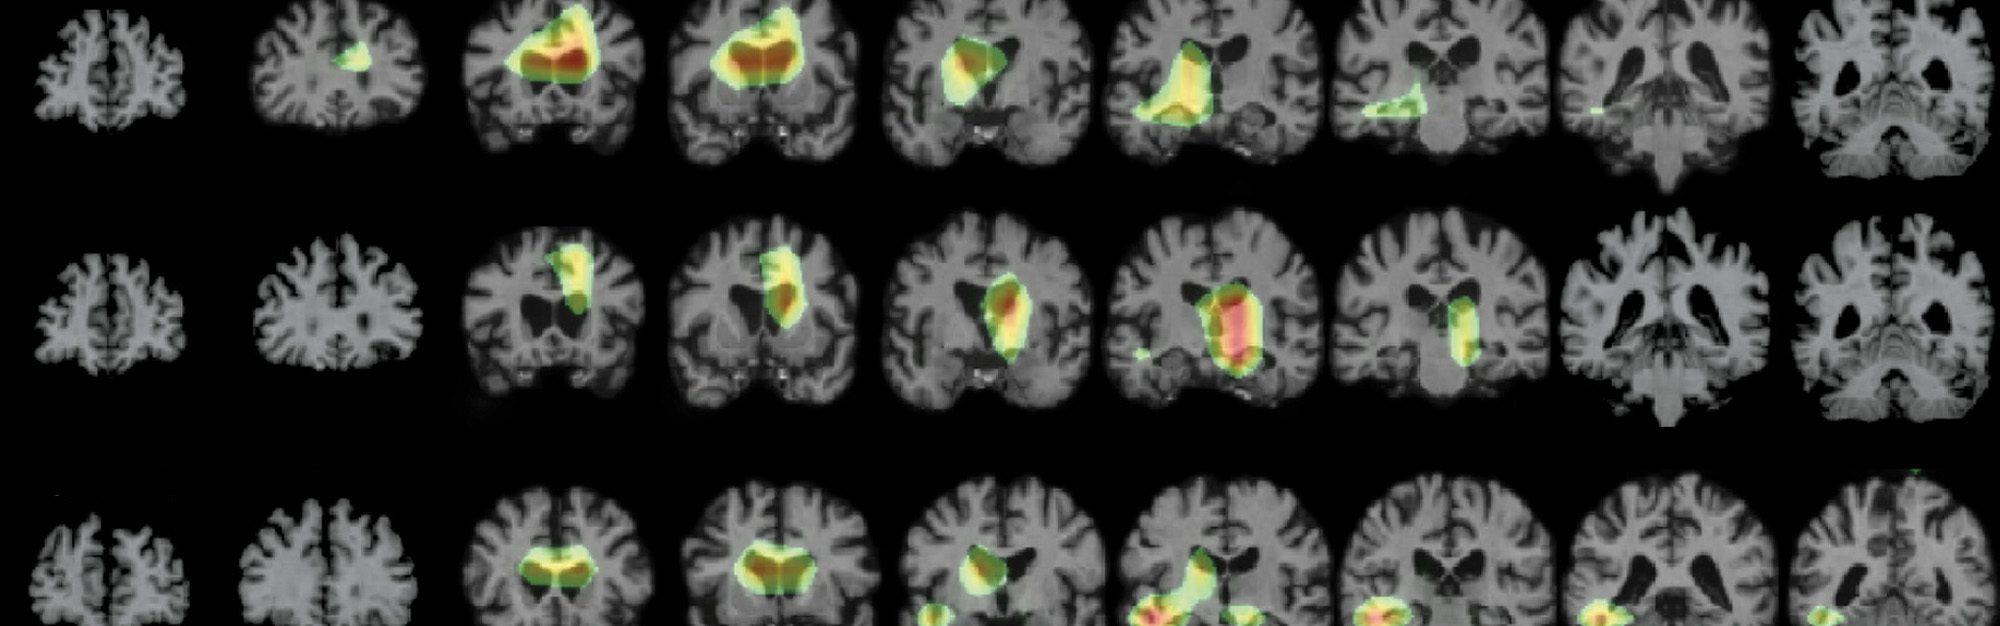

MRI imaging of brains.

Clinical biomedical imaging focuses on the development and application of advanced imaging technologies and artificial intelligence to improve our understanding, diagnosis, and treatment of human disease using modalities such as MRI, PET, CT and ultrasound.